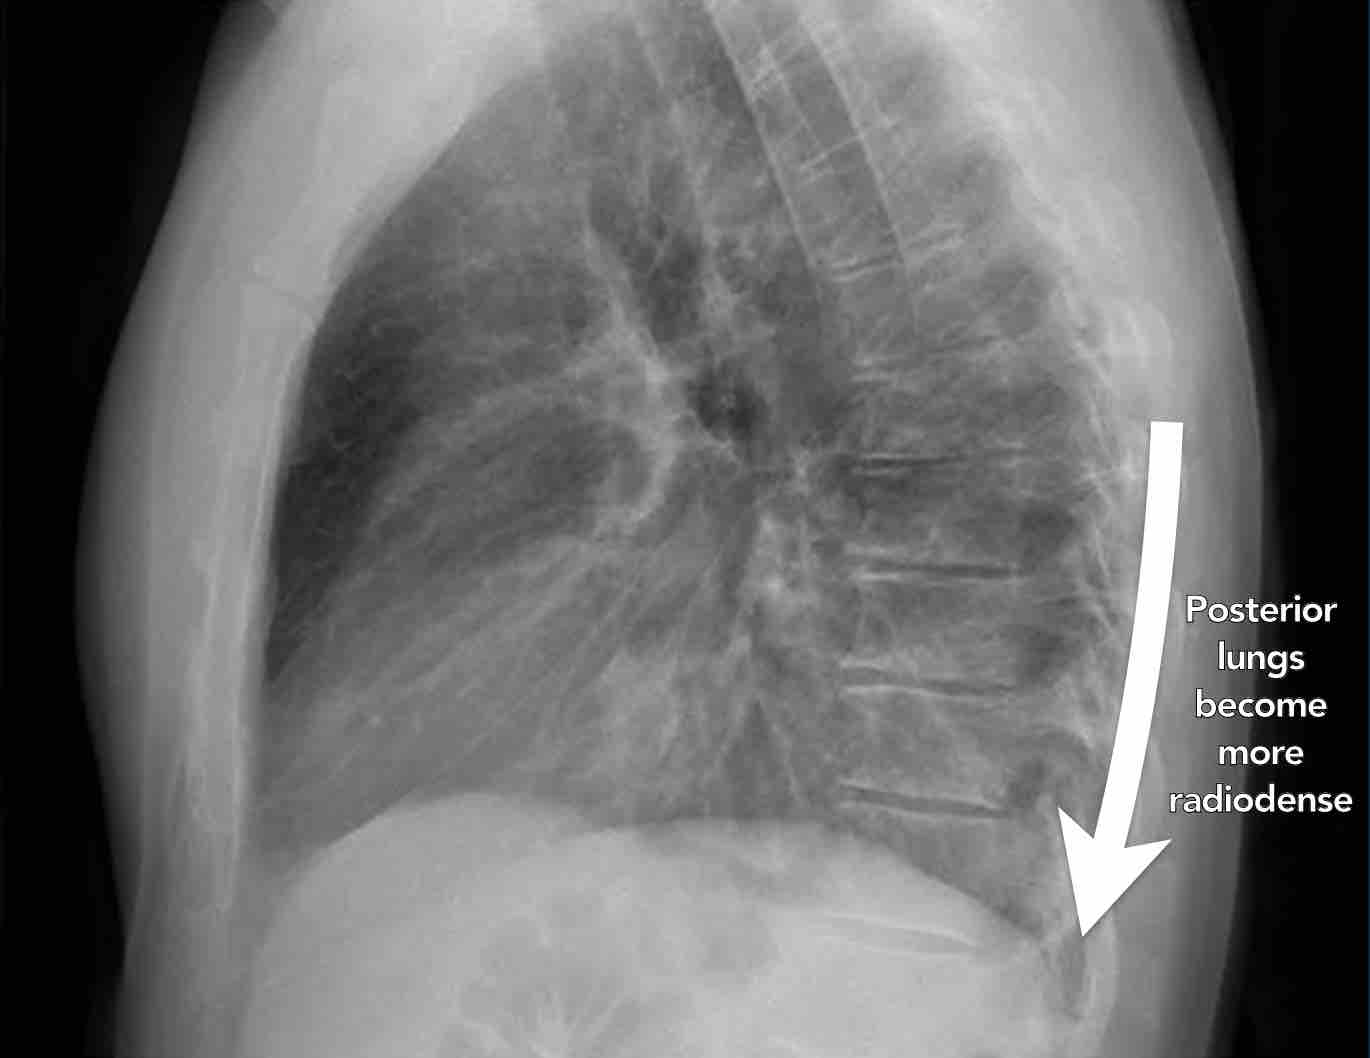

Khi đánh giá các thân đốt sống trên tư thế nghiêng, chúng phải có hình ảnh thấu quang (tối hơn) tăng dần từ trên xuống dưới do lượng phổi có khí chồng lên ngày càng nhiều (mũi tên trắng).

Nếu các đốt sống ngực dưới có hình ảnh đậm bất thường, điều này có thể gợi ý bệnh lý ở các thùy dưới, chẳng hạn như đông đặc hoặc khối — đây được gọi là dấu hiệu cột sống.